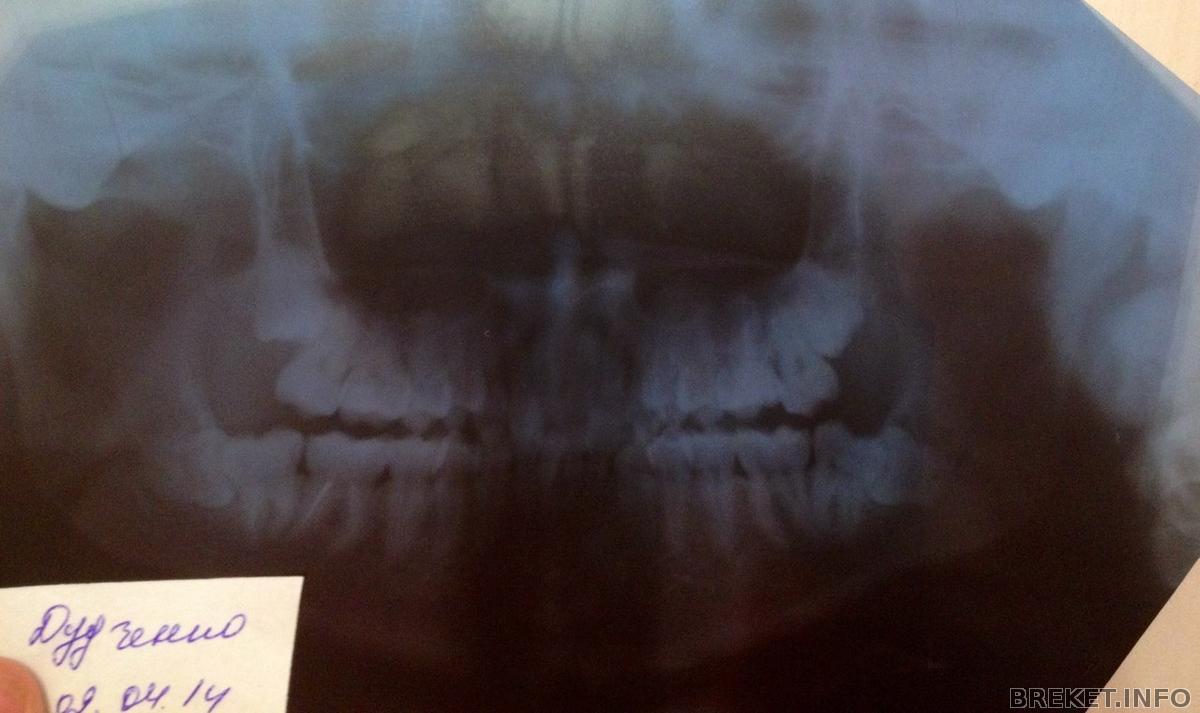

зубки сфотографирую, что бы достать нижнюю 8ку нужно вскрыть слизистую ,причем ее большую часть с вырываемой стороны, это все будет проходить через 7ку, затем нужно выпилить приличный кусок надкостницы , достать эту 8ку не повредив 7ку , ну и потом зашивать, но это все может приобрести обостренный характер...могут быть осложнения..и нервы задеть могут...в общем беда) Спасибо за советы! снимок направлю Андреищеву )

Сочувствую. У вас нижний левый зуб, как у меня верхний правый - растет в 7 так, что надо или сначала 7 удалять потом 8, или разворотить полчелюсти((( Попробуйте обсудить с ортом возможность удаления 5к и стягивания на их место 6 и 7 (в данном случае 8 поспособствуют перемещению этих "тугих" зубов"), тогда и место получите, и 8 может вылезут...

Посмотри на мою восьмерку, она лежала как раз в точно таком же положении, как у тебя (упиралась в 7-ку).